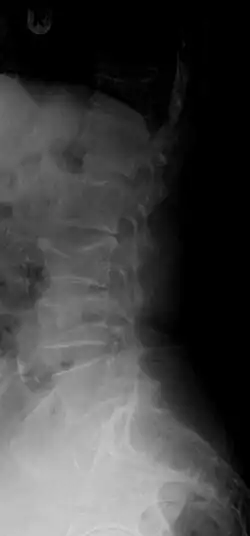

A compression fracture is a collapse of a vertebra. It may be due to trauma or due to a weakening of the vertebra (compare with burst fracture). This weakening is seen in patients with osteoporosis or osteogenesis imperfecta, lytic lesions from metastatic or primary tumors,[1] or infection.[2] In healthy patients, it is most often seen in individuals suffering extreme vertical shocks, such as ejecting from an ejection seat. Seen in lateral views in plain x-ray films, compression fractures of the spine characteristically appear as wedge deformities, with greater loss of height anteriorly than posteriorly and intact pedicles in the anteroposterior view.[3]

Compression fractures are usually diagnosed on spinal radiographs, where a wedge-shaped vertebra may be visible or there may be loss of height of the vertebra. In addition, bone density measurement may be performed to evaluate for osteoporosis. When a tumor is suspected as the underlying cause, or the fracture was caused by severe trauma, CT or MRI scans may be performed.

Compression fracture of T12